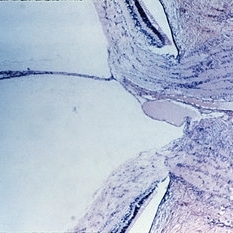

Slide 8-8

Mar 4 2019 by Lancaster Course in Ophthalmology

Localized vitreous traction inducing cystic retinal degeneration and retinal detachment. (E.P. No. 19650)

Condition/keywords: cystic retinal degeneration, vitreous traction